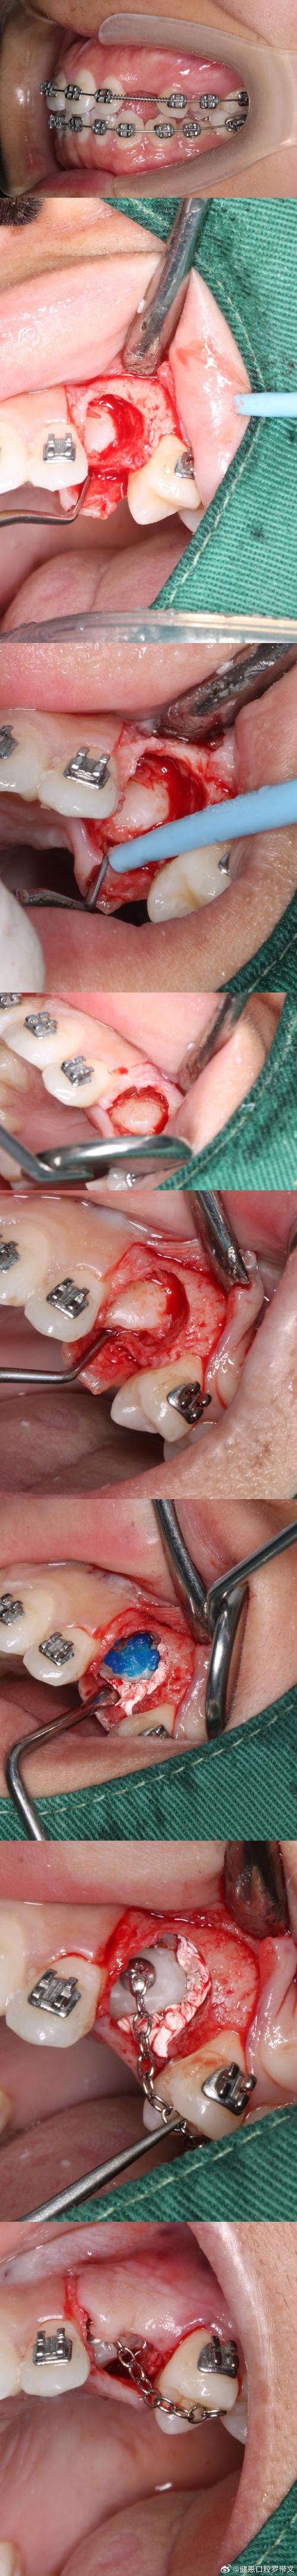

阶段2:外科开窗术

- 目的:暴露埋伏尖牙牙冠,粘接牵引装置。

- 方式:

- 唇侧开窗:适用于唇侧埋伏牙。

- 腭侧开窗:适用于腭侧埋伏牙。

- 翻瓣去骨:去除覆盖牙冠的骨质,暴露牙面。

- 粘接附件:

- 在牙面上粘接正畸托槽或舌侧扣。

- 连接弹性链或橡皮筋,连接到正畸弓丝或支抗钉。